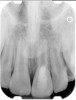

Clinical procedure: Regeneration of the endodontic pulp space is indicated for cases with very thin dentinal walls and an open apex that is more than 1 mm in diameter radiographically (Figure 4). Disinfection of the root canal system is performed using sodium hypochlorite irrigation followed by a triple antibiotic paste dressing that is left in place for 1 week. At the second visit, ethylenediaminetetraacetic acid (EDTA) is used to condition the dentin walls, which results in the release of growth factors, and bleeding is stimulated in the periapical tissues (where stem cells are located), with the aim of filling the pulp space with a stable blood clot, which would serve as the scaffold. MTA is then placed at the canal orifice in contact with the clot to protect it from coronal microleakage (Figure 5 and Figure 6). In time, the clot should be replaced with a reparative tissue of variable composition, and the root walls should continue to thicken due to the deposition of a dentin-like material on the pre-existing root dentin27,28 (Figure 7 and Figure 8).

Fig 4. Preoperative radiograph showing aggressive external root resorption and thin dentinal walls.

Figure 4